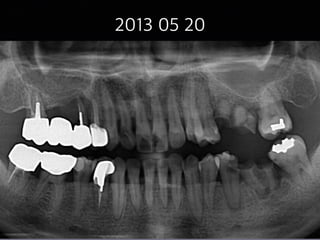

#6,#7,#8,#9,#29

partial pulputomy

follow-up case

(48 female)

2013 05 20

31

2013 06 28

15m later